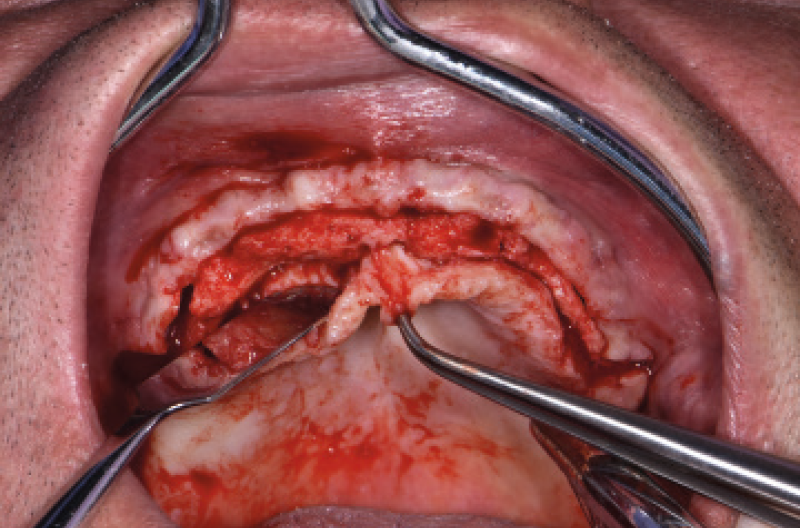

Ho riaperto il mascellare superiore con un lembo a spessore parziale palatino e con scarichi solo distali per limitare al minimo il trauma allŌĆÖosso perimplantare; dopodich├® ho scelto i monconi MUA pi├╣ idonei, tutti GH 1,5 mm uno diritto, tre angolati a 15┬░ e due angolati a 25┬░. Una volta parallelizzati, ho attivato i monconi MUA negli impianti e avvitato gli adattori Conic per trasformarli in monconi MUA-Conic. Dopo aver suturato il lembo, ho attivato le cappette Fixed sui monconi MUA-Conic e poi si ├© proceduto alla ribasatura della protesi opportunamente scaricata in corrispondenza dei monconi MUA-Conic. Durante la procedura intraorale di inglobamento delle cappette Fixed, la protesi si ├© autocentrata in occlusione con la protesi conometrica fissa provvisoria inferiore. Infine la protesi ├© stata rifinita, riposizionata in bocca e attivata (Figg. 30-37). A distanza di un mese entrambe le Toronto provvisorie sono state rimosse e ribasate per un migliore condizionamento del tessuto gengivale (Fig. 38).

Fig. 30 – Riapertura del superiore con lembo a spessore parziale